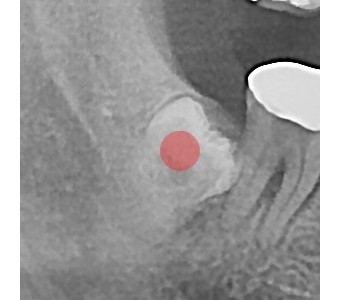

以成果证明实力。

国际摩牙齿科

真实临床案例